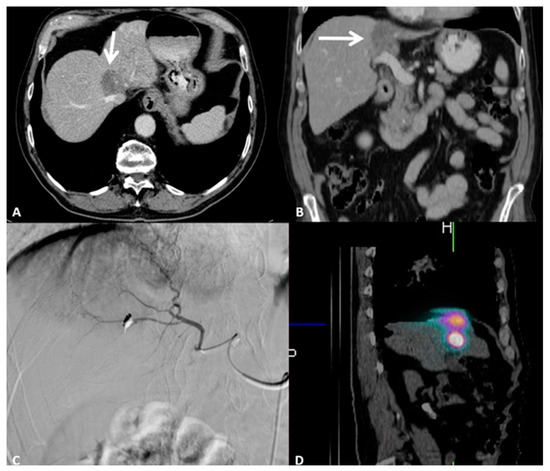

5. Intrahepatic Cholangiocellular Carcinoma

5.1. Locoregional Approaches

5.2. Key Points